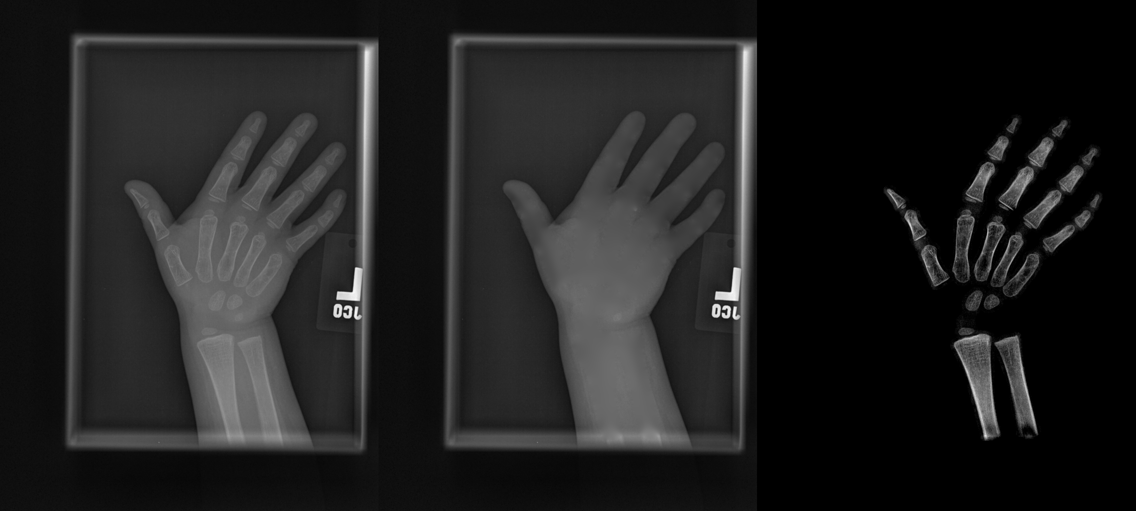

To tackle these problems, we propose to estimate the soft tissue image and bone image simultaneously without losing the linear relationship between image intensity and physical property of the imaging objects. Two examples from our method is shown in Fig. 1. The bone details are enhanced, which is theoretically guaranteed. The details of our method will be explained in later sections.

Several results from our method are shown in Fig. 7. The left column is the original input image. The right two columns are the soft tissue and bone image, respectively. It can be told that the soft tissue image is smooth as we assumed. Meanwhile, the bone image has better image contrast as desired. Moreover, our method can reach real-time performance on these X-ray images. The running time of our method on these images is reported in Table I.

In each panel of Fig. 10, the input image (left) is decomposed into soft tissue (middle) and bone image (right) by our method. Although we only show the first ten images from the data set, the results for the rest images are similar.

The bone images have better image contrast since the parameter is theoretically guaranteed. Such enhancement can also be directly told by radiologists. Such enhancement is good for bone diagnosis in practical applications.